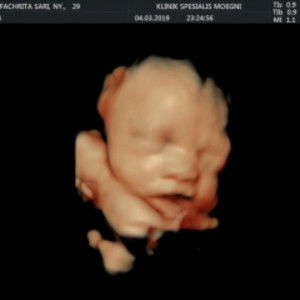

ibu2 klo bayi baru lahir pke popok kain smp brp lama?merk pampers yg rekomend bayi lahir?